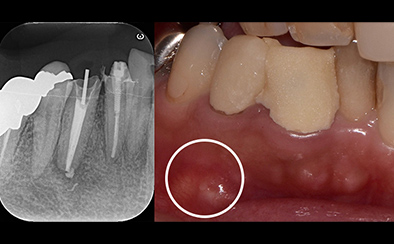

治療前

治療後

写真の白丸部分に膿が溜まっていて痛みと腫れがあり、半年も続いているそうです。これを治療した歯科医師はこれで治らなかったら抜歯してインプラント治療という選択をしました。

歯の状況や、顎骨の状況、また、患者さんご自身からもできるだけ自分の歯を残したいというご希望だったので、精密根管治療を天然歯の保存を目的として計画しました。

まず、根管内のガッタパーチャ(根管充填材)を除去、さらにマイクロスコープによる拡大視野とラバーダム防湿法により丁寧に汚れを除去しました。根管内の感染源がなくなったことを確認したうえで、通常のガッタパーチャとシーラーでは緊密な根管充填ができないと診断し、患者さんに説明したうえでMTA (ProRoot MTA)を選択しました。

3回の治療を行った後、痛みと腫れ、また上の画像にあった丸印の膿の袋もなくなっています。ということは、インプラントせずにこの上にクラウンを被せて治療を終了することができます。

| 費用 | コア除去:22,000円 根管治療:132,000円 MTA根管充填:33,000円 合計:209,000円 |

|---|---|

| リスク・副作用 | 治療中に一時的な咬合痛や冷温水痛、若干の歯肉の腫れ、発赤などを生じることがあります。また仮歯の時期には仮歯の脱離や破損の可能性、舌感などに違和感を覚えることがありますが、本歯に移行するまでに通常消失します。 ※すべて症例による違いや個人差があります。 |

※表示金額は全て税込みです。